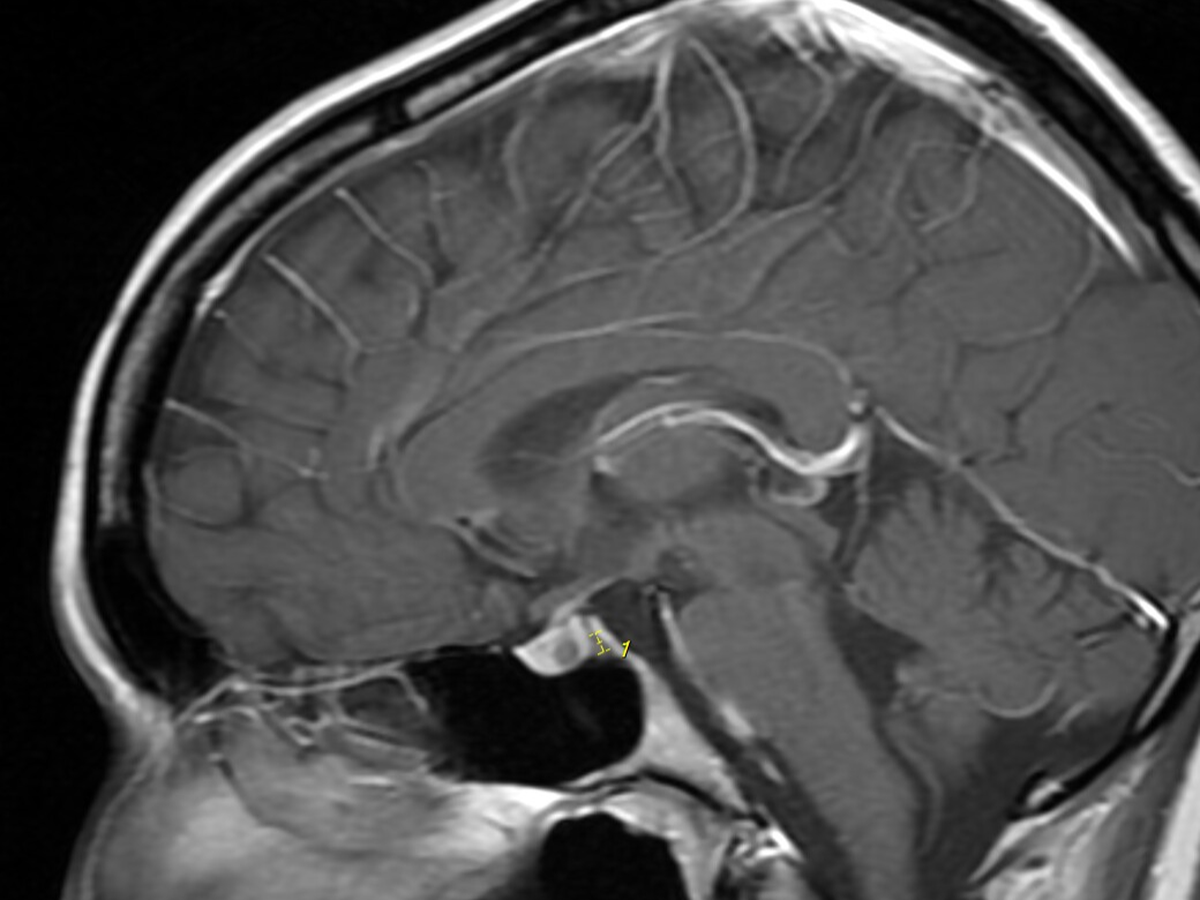

My name is Bri, and I am 22 years old. I've been experiencing migraines, balance changes, and vision changes. I was referred to a neurologist, and they ordered a brain MRI, where they found a tumor in my pituitary gland that is causing these problems. This tumor is also messing with my hormones and causing low cortisol, which was tested by my neurosurgeon. My surgery will be performed on April 7, and I was told I need to be on medical leave from my job for at least a month. It will be hard for me to stay out of work since I have a few bills that I need to take care of, and I do not want to stress about them while I am recovering. I want to have a stress-free and good recovery. My family will be with me while I recover. Thank you for reading.